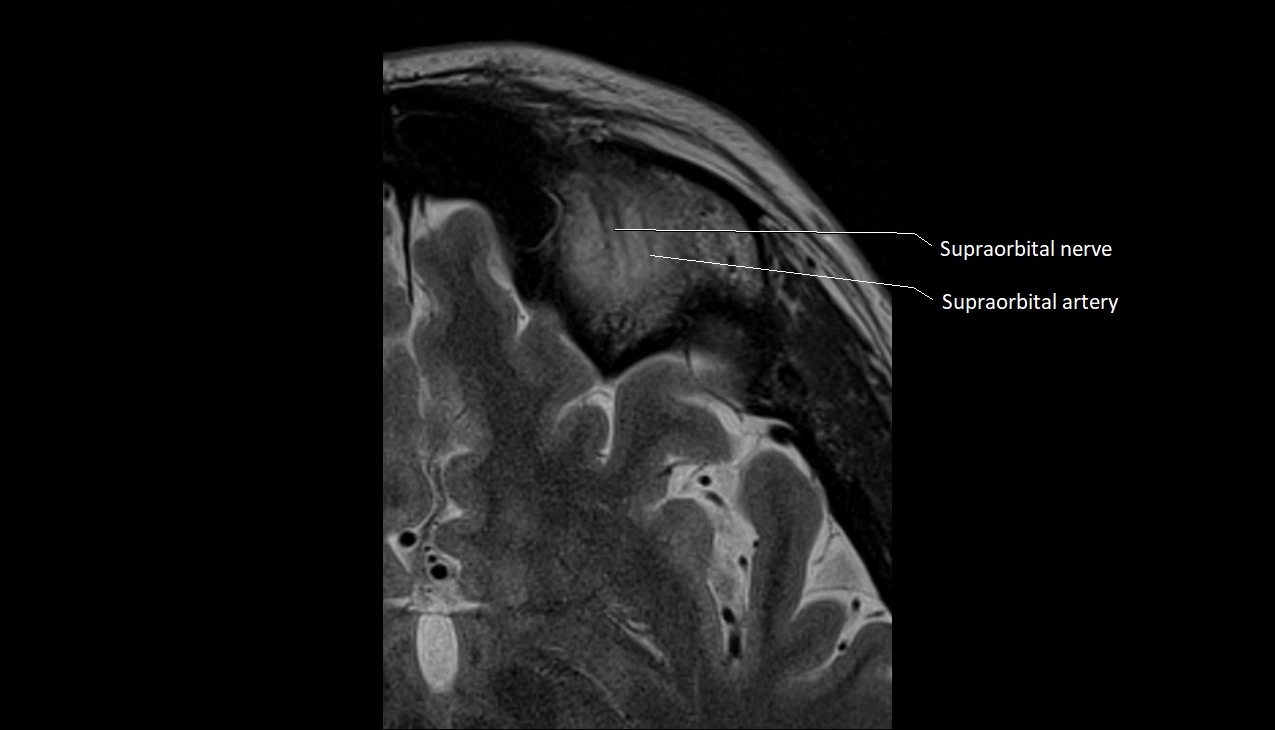

- Supraorbital artery

- Supraorbital nerve